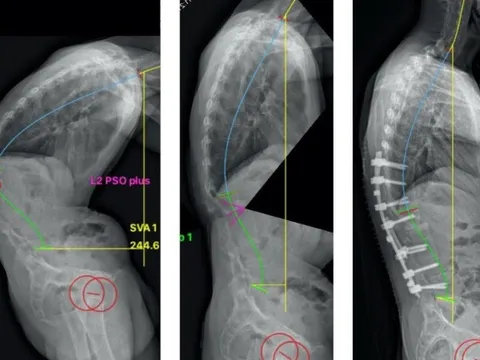

Bệnh loãng xương không điều trị kịp thời sẽ gây hậu quả xấu

Đó là chia sẻ của Ths.Bs chuyên khoa 2 Võ Hòa Khánh, Trưởng phòng Quản lý chất lượng, Bệnh viện Chấn thương chỉnh hình Tp.HCM.